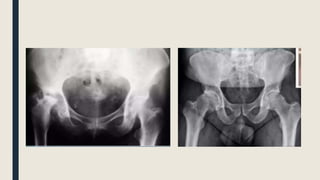

IMAGEN

■ AP Pelvis

– Línea de Shenton

– Descartar Fx

– Proyección Judet (45º)

■ Fragmentos osteocondrales / lesión acetabular

■ TAC / RMN

IMAGEN ■ AP Pelvis –Línea de Shenton – Descartar Fx – Proyección Judet (45º) ■ Fragmentos osteocondrales / lesión acetabular ■ TAC / RMN